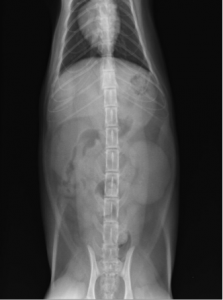

術前のレントゲン

VD像では不明瞭だがラテラル像にて腎臓の尾側に結石が確認できます。